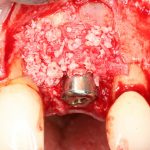

Рекомендации по установке имплантов. Для всех. Часть V.